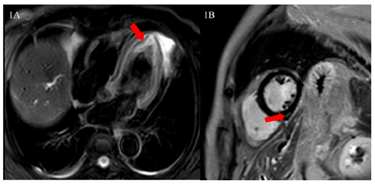

心脏增强MRI(2023年7月12日):可见左室心尖部心肌水肿(图1A),左室下壁延迟强化(图1B)。

患者66岁老年女性,亚急性病程,急性加重。原发病诊断明确,肝内胆管癌,多发转移,失去手术时机,接受了免疫、靶向和放射治疗。心内科相关主要特点是恶性肿瘤药物治疗后心肌损伤标志物升高和动态变化,停用药物-应用激素后仍有波动,肌钙蛋白最高1.0,应用激素冲击治疗后心肌损伤标志物有所下降。整个过程中患者无明显心脏相关的症状,无胸闷、憋气、心悸、胸痛,活动耐力无下降。既往有卵巢交界性肿瘤和手术病史,农民,无毒物接触史,无烟酒史。查体生命体征平稳,心肺无明显阳性体征,主要阳性体征腹部胆管引流。心电图:新发RBBB,超声心动图:左室壁运动未见明显异常,未见节段性室壁运动异常,形态正常,未见心尖膨出,传统左室收缩功能指标正常62%,更敏感的GLS减低。心脏磁共振检查证实存在心肌水肿。综上,心肌损伤病因考虑药物性心肌炎可能性大。

国内近期也发布了ICIs相关心肌炎临床诊疗实施建议[4]。其诊断标准包括病理学诊断和临床诊断。病理学诊断因其有创性,临床难以推广,目前主要依赖临床诊断:肌钙蛋白明显升高加1条主要标准或2条次要标准,但需除外急性冠脉综合征及感染性心内膜炎[4]。主要标准是:心脏磁共振诊断为急性心肌炎。该患者肌钙蛋白明显升高合并1条主要标准,符合ICIs相关心肌炎临床诊断标准。